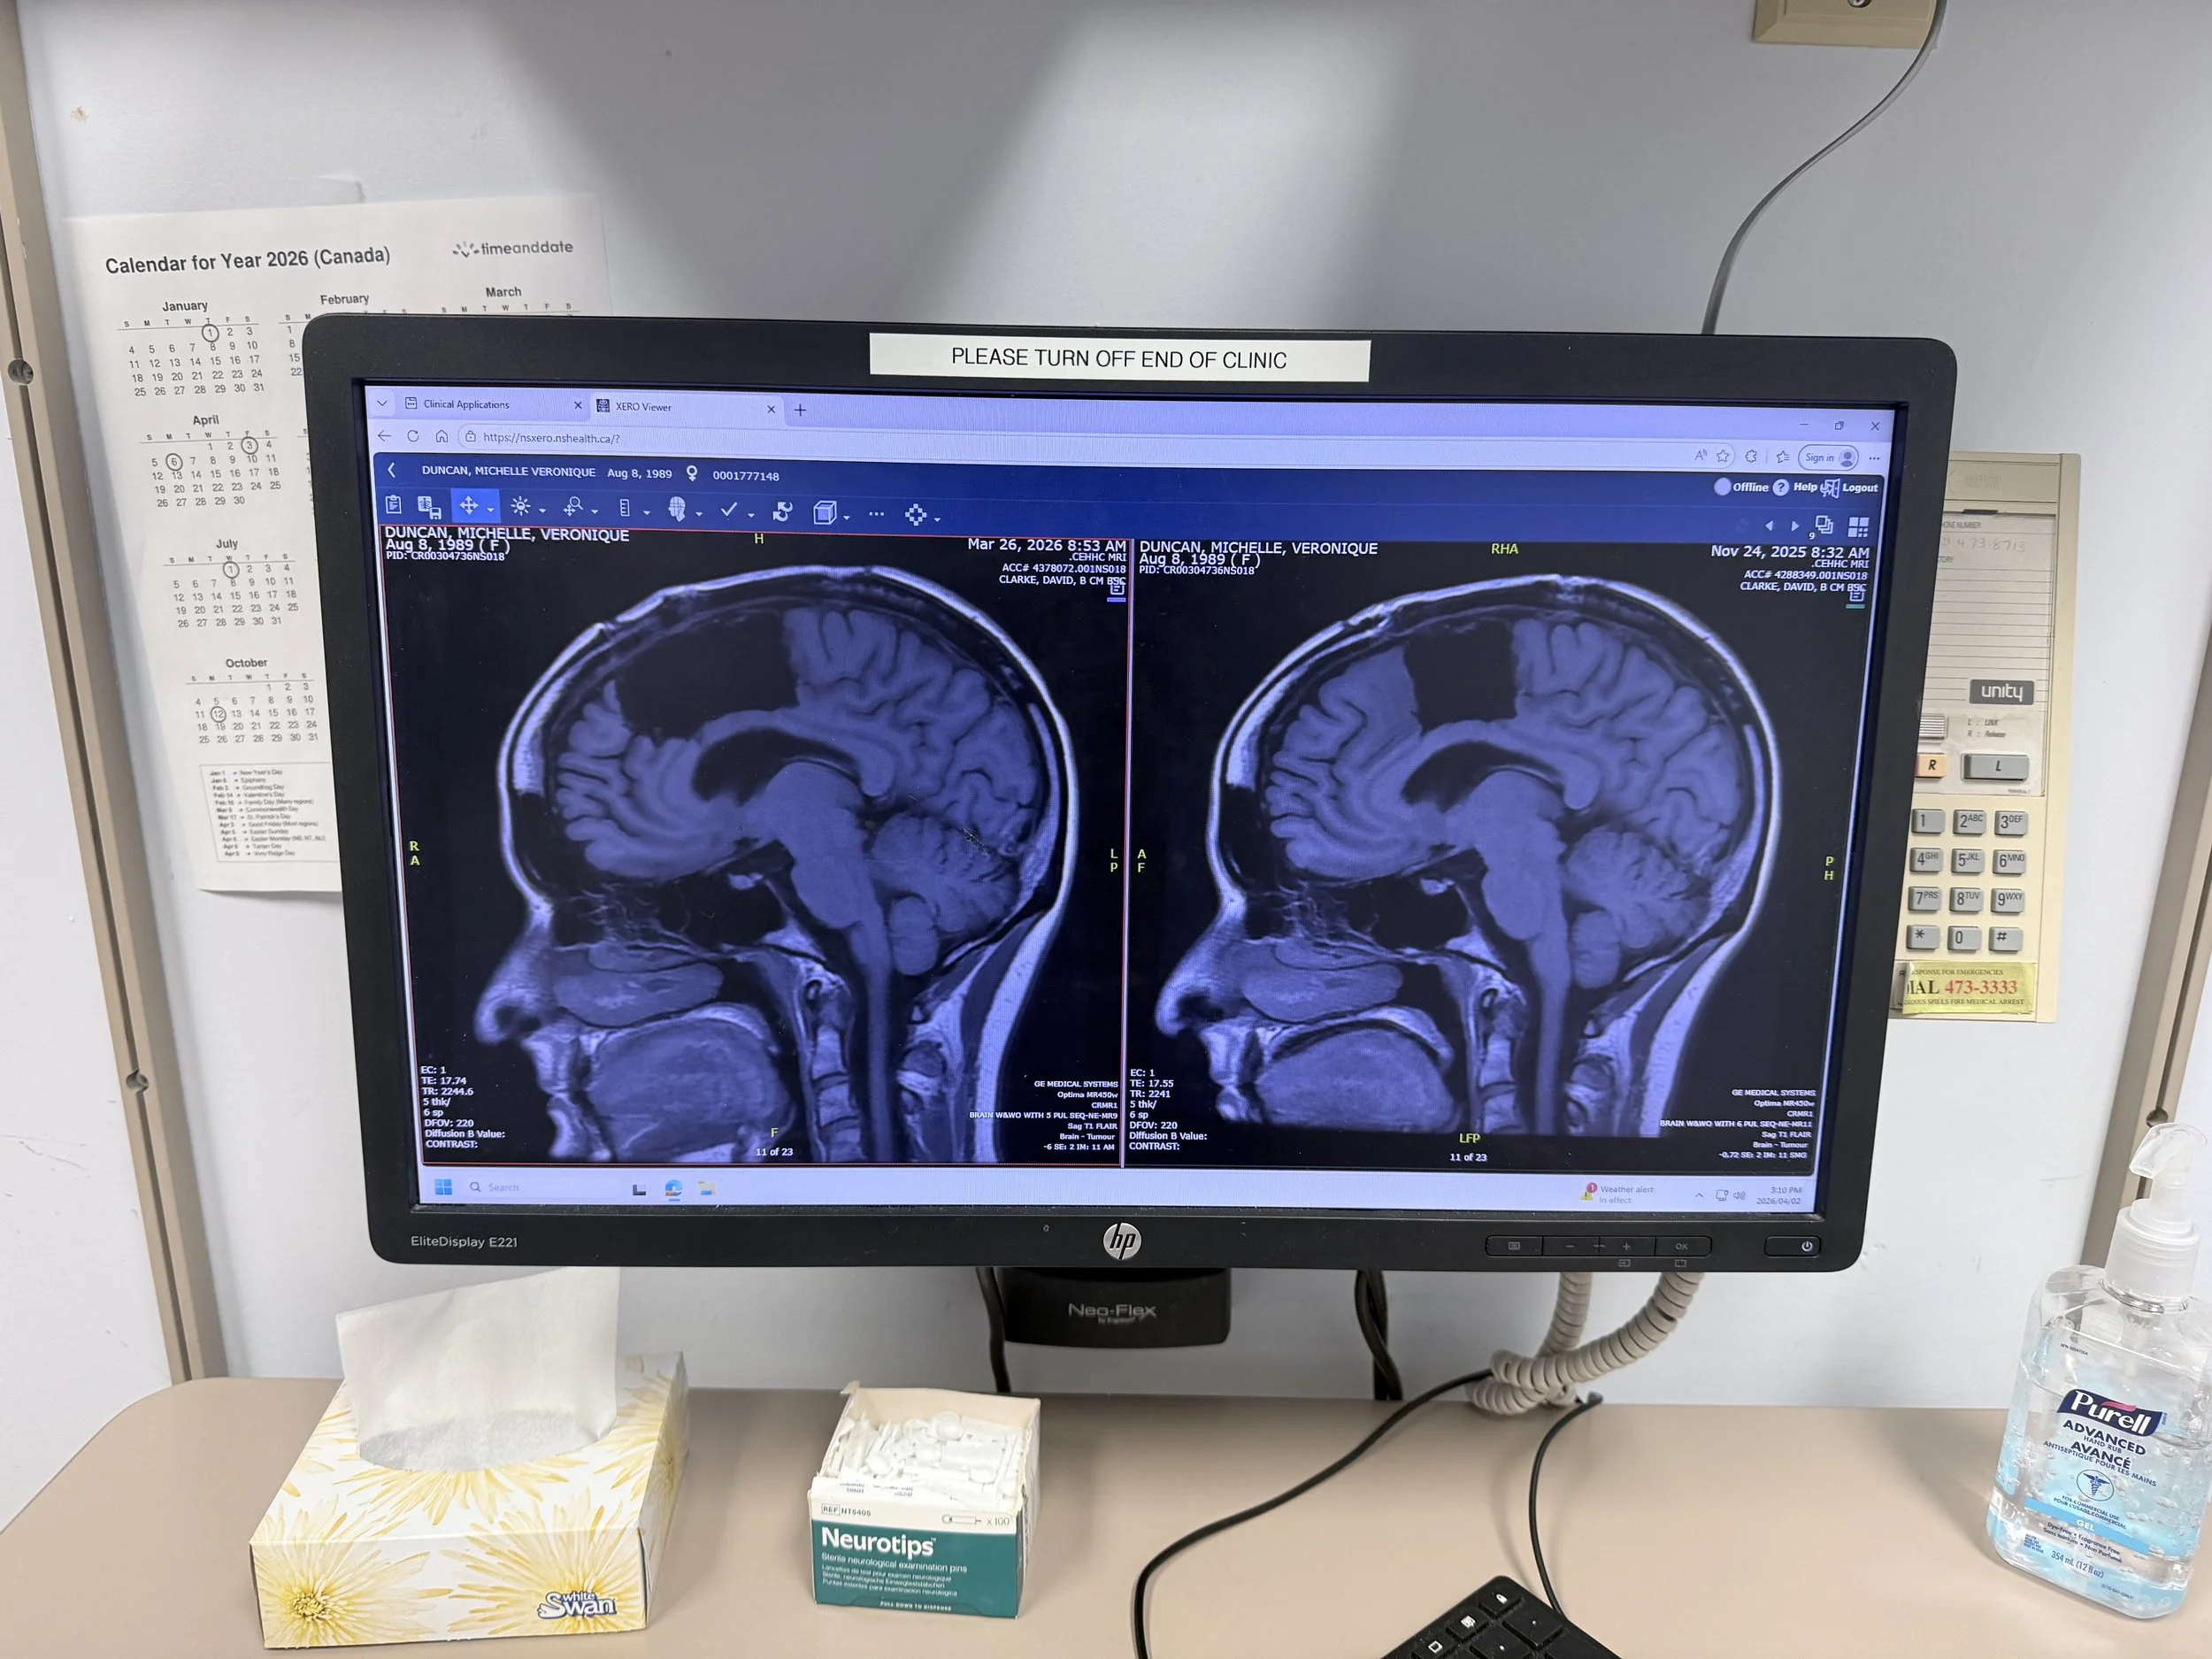

“A Picture is Worth a Thousand Words”

I had another MRI last week and met with my surgeon again.

He was really happy with how I was doing. When he pulled up my MRI, all I could say was, “WOW.”

He smiled and said, “A picture is worth a thousand words.”

And honestly—it really was.

He told me it was the best outcome we could have hoped for, given my circumstances.

I got emotional. Even though this journey has been incredibly difficult, I felt so thankful that we chose to move forward with the second surgery, and I told him that.

A Note Before the Images

Below are photos of my MRI, shared in the order they were taken.

If you’re sensitive to this kind of content, I would gently advise not scrolling further.

This is your WARNING.

On the right you can see the tumour where the cursor is pointing.

On the left you get a better idea of how it is diffused in the brain and the area that was affected.